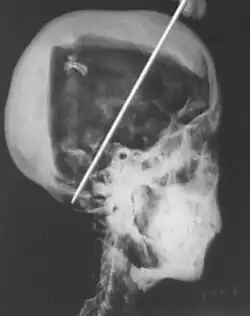

Acontece que, por causa da fama, a múmia de Tutankhamon foi examinada muitas vezes, seu rosto inclusive foi recriado por computador. Em 1963 a múmia passou pelo raio X, em 2005 foi examinada usando tomografia computadorizada.

Em 1963 se descobriu que havia um ferimento na base do crânio da múmia, o que poderia ter sido causado por um golpe. Isso teria levado o faraó a morrer. Então seria assassinato ou um simples acidente?

Se foi acidente, ele deve ter caído do carro de guerra. Será? Se o rei Tut morreu por causa desse ferimento e foi assassinato, quem o matou e por quê?